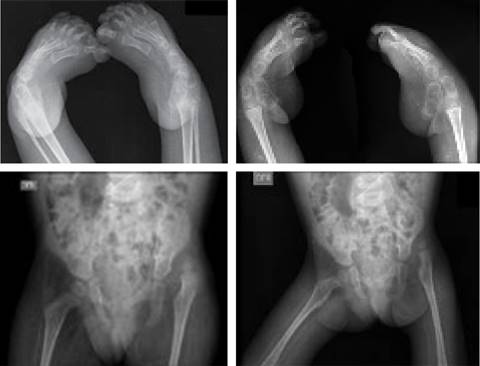

Lactante femenino de 22 meses, producto del primer embarazo de padres no consanguíneos sin historia familiar de enfermedades. Nació por parto vaginal, a las 32 semanas de gestación, con requerimiento de oxígeno por mascarilla y con múltiples hospitalizaciones por traqueítis. Al mes de vida se le realiza gastrostomía y a los dos meses traqueostomía por disposición de distractores faciales, lo cual estaba asociado a debilidad en extremidades, contractura muscular, dificultad y alteración en la marcha, coxa valga, genu valgo y pies planos; por lo que se sospechó de displasia ósea. Por ecocardiograma, no se detectó cardiopatía congénita. Mientras que radiológicamente se confirma deformidad en pie equino varo bilateral y luxación congénita de cadera izquierda (Figura 1).

Figura 1: Informe radiológico que confirma deformidad en pie equino varo bilateral y luxación congénita de cadera izquierda.